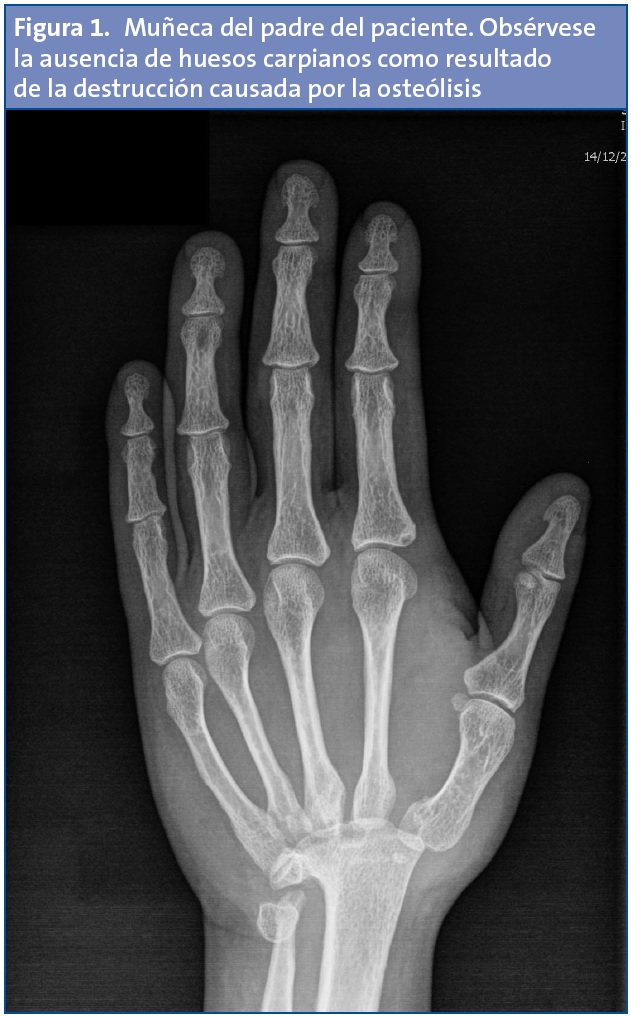

El padre tiene una talla de 180 cm, pero su envergadura está reducida a 164 cm. Su mano mide 18,7 cm de longitud (resulta acortada 4 cm para su estatura) con un tercer dedo de 8,3 cm (normal). La radiografía paterna muestra ausencia bilateral del carpo (Fig. 1).

El resultado final de la osteólisis conlleva una disminución de la braza de los sujetos afectados (a expensas de la desaparición del carpo) con modificaciones en la estructura de los pies según los daños tarsianos. Las alteraciones funcionales derivadas de la destrucción ósea son variables: algunos pacientes quedan muy afectados mientras que otros (como el padre de nuestro paciente) padecen muy escasas repercusiones.